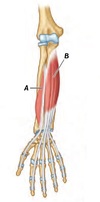

Name muscles A and B

A - Flexor pollicis longus

B - Flexor digitorum profundus

Name muscles A to D

A - Pronator teres

B - Flexor carpi radialis

C - Palmaris longus

D - Flexor digitorum superficialis

Name muscles A to E

A - Pronator teres

B - Ulnar head of pronator teres

C - Flexor carpi radialis

D - Palmaris longus

E - Flexor carpi ulnaris